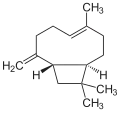

Let's start with some background on marijuana chemistry. Relevant chemicals in marijuana fall into two broad classes: cannabinoids (which in plants are specific to the Cannabis genus) and terpenoids (which are widespread in many plants).[7][8] Humans and other animals, produce endocannabinoids, which are different than but in the same chemical class as those cannabinoids found in cannabis. The main psychoactive chemical in marijuana is tetrahydrocannabinol (THC). Another important cannabinoid is cannabidiol (CBD), which is not psychoactive but has many claimed health benefits. Terpenoids in cannabis include ocimene, myrcene, β-caryophyllene, limonene, pinene, myrcene, linalool.